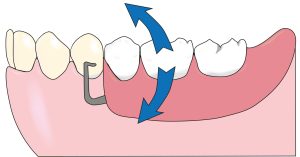

Throughout the mouth preparation process, the diagnostic model should be with the dentist on the analyzer table, positioned at the appropriate inclination to the path of insertion. Thus, the relationship between the diamond bur and the tooth surface to be shaped is projected from the model into the mouth (Figure 10-18).

a) The relationship between the tooth surface shaped in the diagnostic model on the analyzer table and the bur.

b) Preparation made by projecting the relationship between the bur and the model into the patient's mouth.